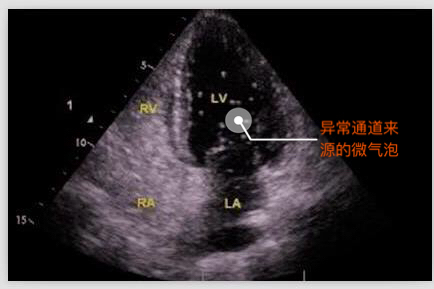

右心声学造影又称发泡实验,是通过经手臂静脉注射造影剂,使微小的气泡进入心腔来显示心腔的血流情况。

由于微气泡直径平均约15微米,正常情形下微气泡从静脉血管输入后只出现在右心,如果在患者的左心房或者左心室看到有微气泡,则提示可能是从异常的通路由右心腔到达左心腔,即常说的右向左分流。同时,检查中还可以根据微气泡在左心腔室出现的时间早晚初步判断异常是出现在心房心室间隔的缺损,还是出现在心外结构的异常,例如肺动静脉瘘等。